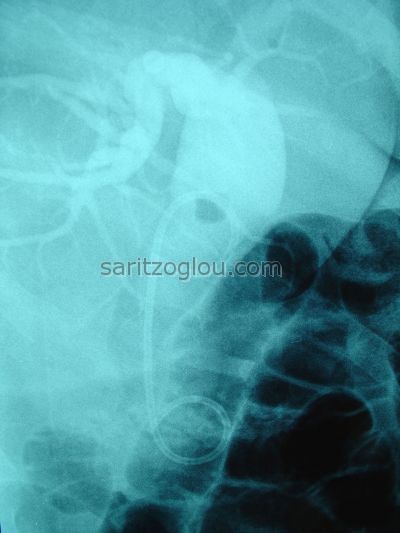

Παρουσία τριών λίθων εντός του χοληδόχου πόρου. Σκιαγραφείται το χοληφόρο δέντρο, τμήμα του κυστικού πόρου και της χοληδόχου κύστης.

Παρουσία δύο λίθων εντός του χοληδόχου πόρους. Διάταση χοληδόχου πόρου λόγω, μερικής απόφραξης του, από την λιθίαση.